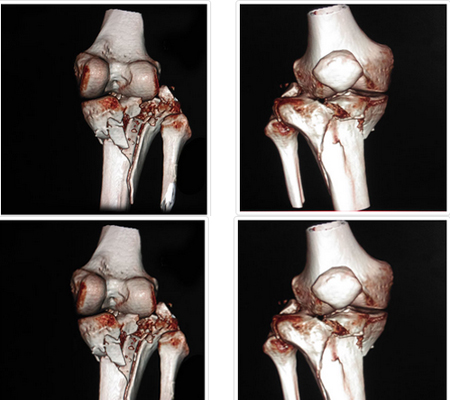

Complex Trauma Surgeries

Fractures and traumatic injuries happen unexpectedly. And while there's no way to prepare for such an injury, it's comforting to know you are in experienced hands. Our experienced surgeons are expert in handling Orthopaedic Trauma situations and perform minimally invasive surgery.

How are complex trauma fractures treated?

The management of fractures has improved considerably with excellent outcomes over the last few decades. These excellent outcomes can be obtained through early intervention by staying relatively active whilst keeping the fractured segment immobilised and subsequent rehabilitation to increase strength and range of motion.